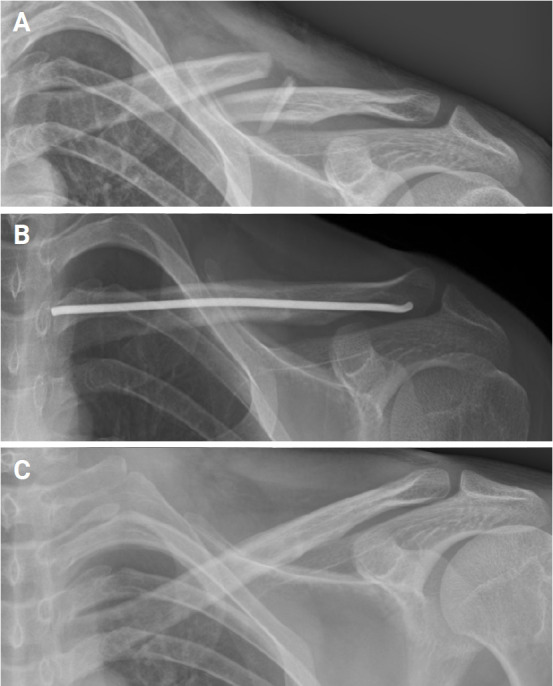

Background: This study aimed to compare the outcomes and complications of active young adults undergoing open reduction and plate fixation (ORPF) and intramedullary nailing (IMN) for displaced midshaft clavicle fractures (MCFs).

Methods: A retrospective review was performed on all patients undergoing ORPF and IMN of complete MCFs at a single center between 2018 and 2022. Patients who were younger than 60 years with radiographic follow-up until union were included in the study. The mean age of the patients was 33.1 years. Outcome measures were achievement of union, time to healing, residual deformity, complications, and need for additional procedures.

Results: Of 39 patients, 29 underwent ORPF and 10 underwent IMN. Plate fixation provided faster functional recovery in the first 6 months, but no difference was observed after 1 year. All fractures in the IMN group healed (100%), compared to 90% in the ORPF group (P=0.08). Mean time to union was 21±8.9 weeks and was significantly different between the two groups (P<0.01), with the ORPF group averaging 23.1 weeks and the IMN group 20.8 weeks. Nonunion rates were higher in the ORPF group (10.3%) than in the IMN group (0%), but the difference was not significant (P=0.08).

Conclusions: Both methods restored patients to their pre-injury functional levels. However, IMN, with its higher healing rate, fewer required revision surgeries, and lower incisional numbness, appears to be the preferred method for treating MSFs without comminution in young adults. Level of evidence: III.